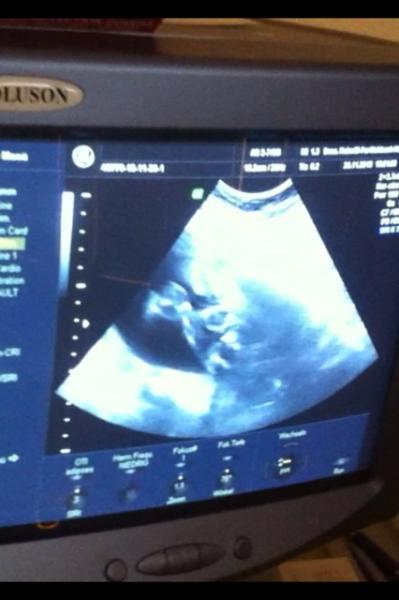

Antwort auf Beitrag von @Jade@

Beine angewinkelt von der Seite betrachtet :)

Bild zu